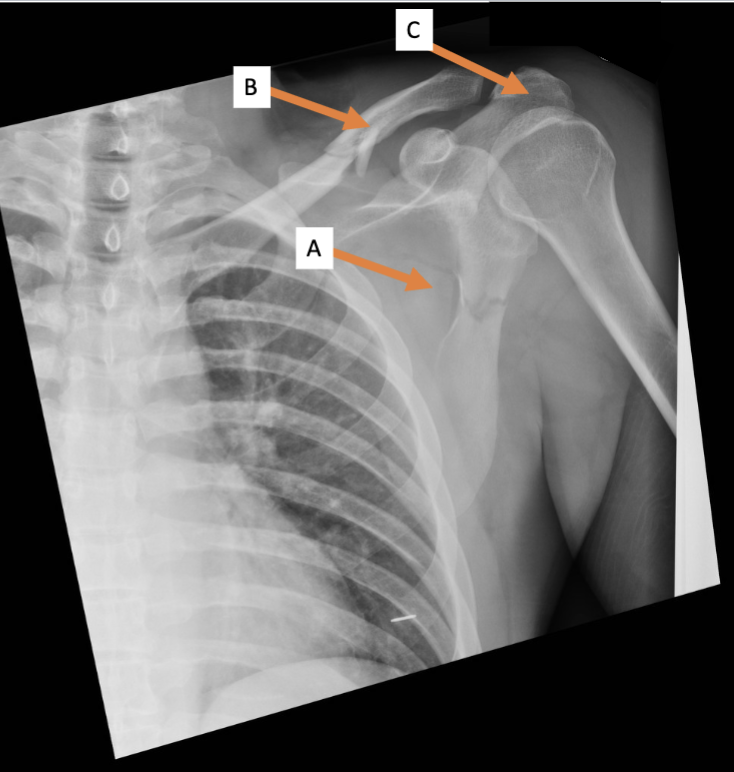

A. Identify structure

Transverse foramen; Vertebral a.

B. Identify structure; What goes through this feature?

Transverse process

C. Identify structure

Scapula

A. Identify the bone

Clavicle

B. Identify the bone

Acromion process

C. Identify the structure